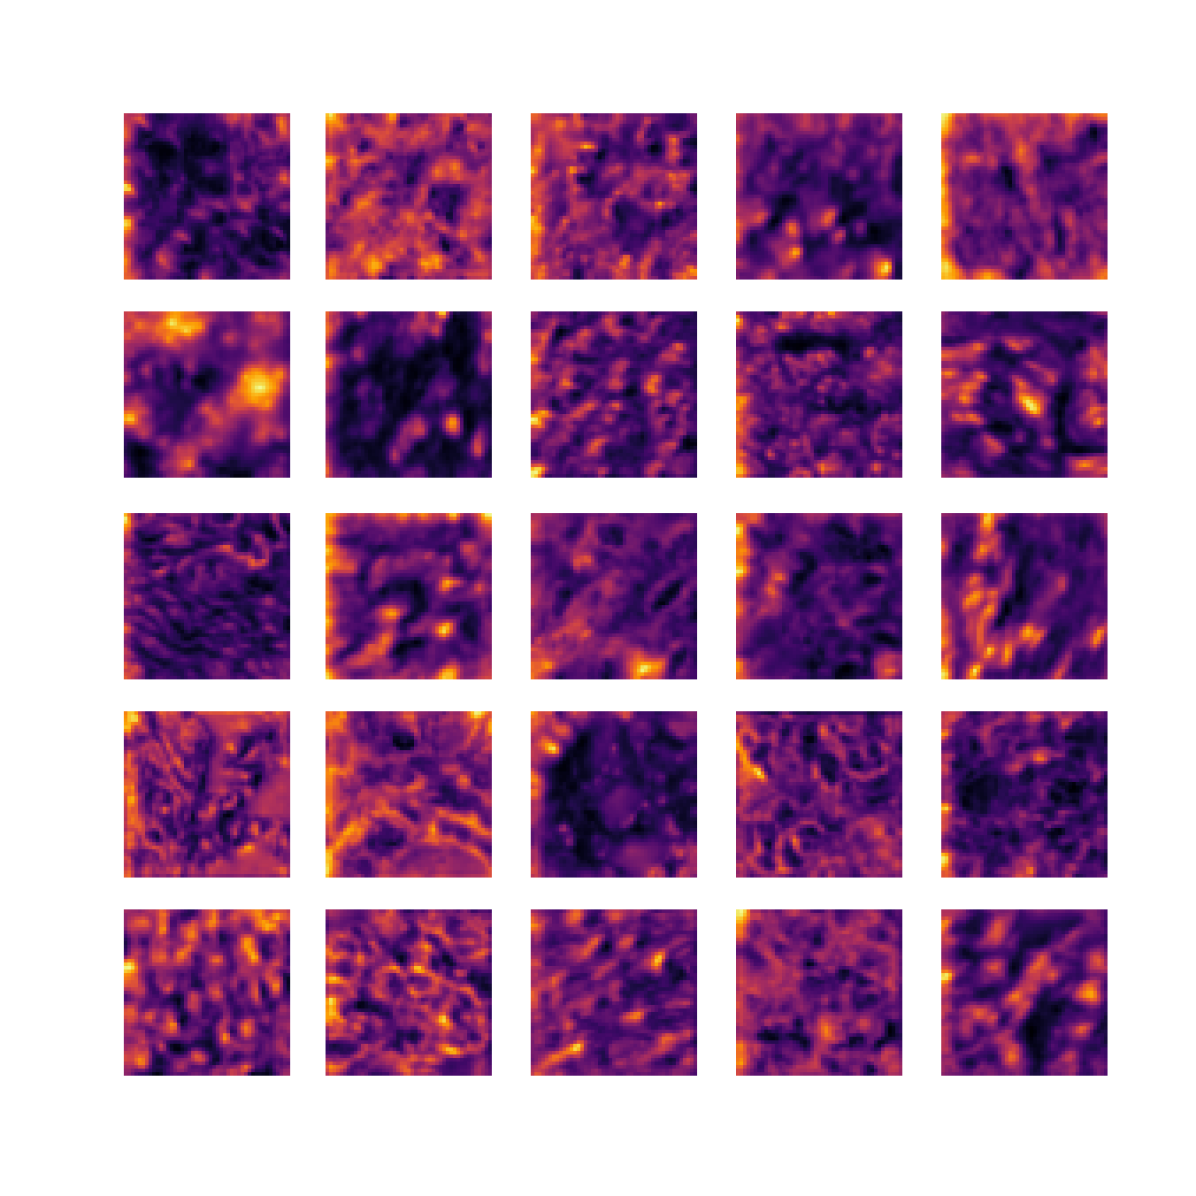

We also analyse the activation maps for each model using GradCAM as described in section S3. This offers more insight into the areas of the image which are contributing most heavily to the models’ representations. In Figure 4(b) we present some representative examples, however, a larger selection which was chosen at random is presented in Figures S10 to S25. The larger selection makes it easier to see the emergent patterns, including that privileged Siamese models tend to mainly identify features which are strongly present in both inputs, while unprivileged Siamese models tend to learn more diffuse features that are not specific to one cell phenotype or image region. TriDeNT ♆ incorporates both sets of features, learning both features specific to the privileged data and more the general features associated with unprivileged Siamese networks.

We can see in Figure 4(b) panel A that for ERG, the privileged Siamese model focuses almost exclusively on any nuclei which could be endothelial cells. As there are very few endothelial cells in the dataset, it could be an effective strategy to identify anything that could potentially be an endothelial cell to minimise the difference between the representations of the H&E model and the IF mask model. In the corresponding unprivileged Siamese image, we see that the model identifies some of these nuclei, albeit less strongly, but also focuses heavily on the other tissue and even the background, while strongly fixating on two spots of debris in the center of the image. This model has less ‘incentive’ to learn the weak features related to endothelial cells as these occur rarely and are not easy to detect, while more generic strong features such as the presence of connective tissue and the prevalence of background are more common and predictable from augmented images. We see that TriDeNT ♆ combines these two feature sets, strongly identifying nuclei while also identifying the connective tissue.

In panel C we see a similar pattern, with the privileged Siamese model fixating solely on the nuclei, while the TriDeNT ♆ model takes a more balanced approach. The unprivileged Siamese model appears to focus on a single cluster of nuclei while neglecting others, and similarly identifies an area of fibroblasts with its distinctive pattern but does not others.

In contrast to panels A and C which represent models with poor privileged Siamese results, panels B and D represent models whose privileged Siamese results were comparable to both TriDeNT ♆ and even the supervised baseline. It is therefore interesting to note that there are far more similarities between the privileged Siamese and TriDeNT ♆ models in both cases. Particularly in panel B, TriDeNT ♆ and the privileged Siamese model return virtually identical heatmaps, with both strongly identifying epithelial nuclei and neglecting the same areas of connective tissue. The unprivileged model in this case appears to focus solely on the centre of the image, giving a significantly different heatmap to the other panels.

Panel D again shows the previous pattern, with the privileged Siamese model identifying the features strongly present in the privileged data – fibroblasts – while neglecting the nuclei present. TriDeNT ♆ also strongly identifies the connective tissue, but, unlike the privileged Siamese model, does not completely neglect the nuclei. The unprivileged Siamese model primarily identifies background, and does not appear to identify the nuclei in this example.